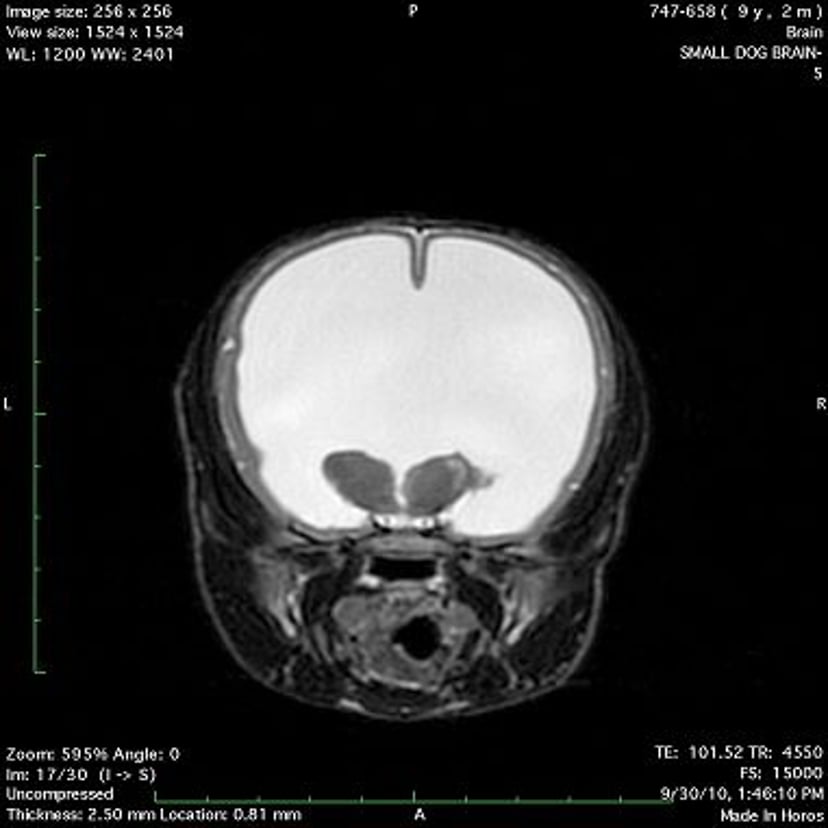

Hydrocephalus, dog (MRI)

T2-weighted transverse MR image of a dog with hydrocephalus showing the dramatic enlargement of the lateral ventricles (the fluid-filled ventricles appear white in this image).

Courtesy of Dr. Rebecca Packer.